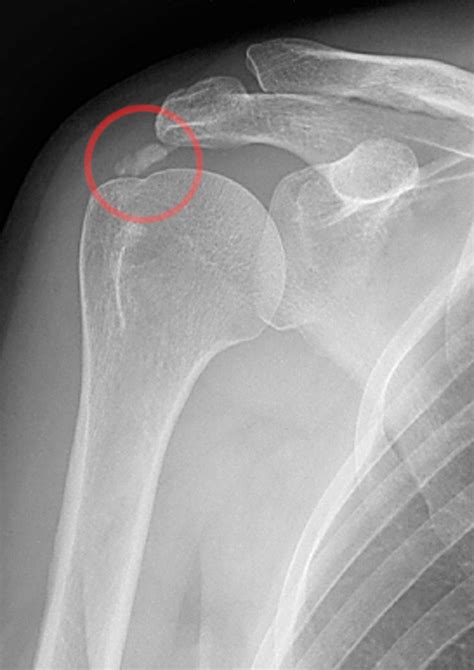

Diagnosing calcification tendonitis involves a combination of physical examination and imaging tests. The diagnostic process typically includes:

• Physical examination: A healthcare provider will assess the range of motion, strength, and tenderness in the affected area.

• Imaging tests: X-rays, ultrasound, or MRI scans can help visualize the calcium deposits and assess the extent of the damage.